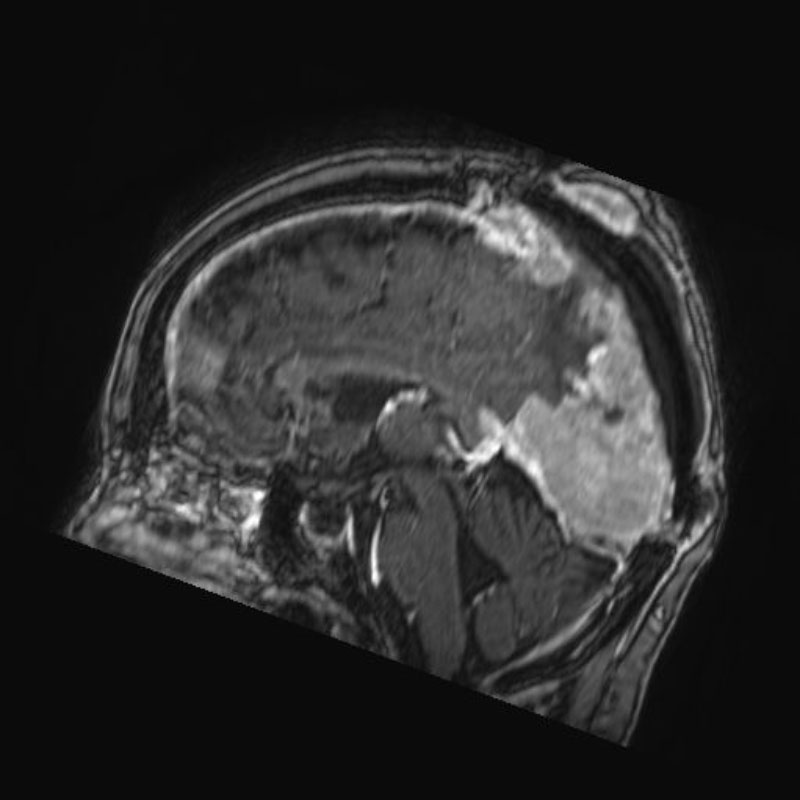

手術前1

手術前2